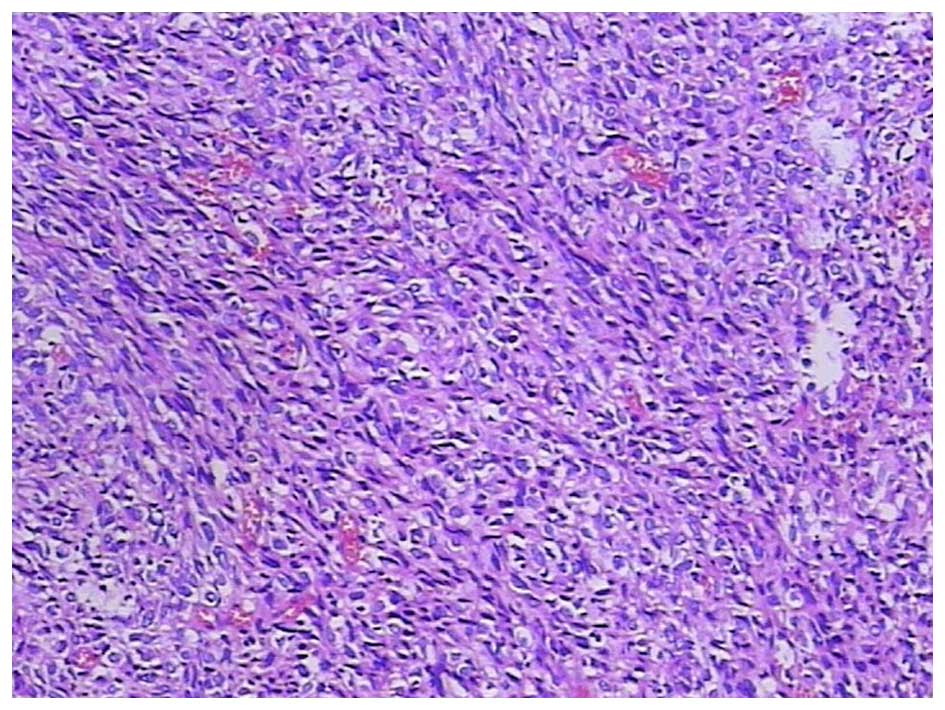

Figure 4.

Epithelioid differentiation with perinuclear and cytoplasmic vacuolization. Hematoxylin and eosin stain; magnification, ×100.